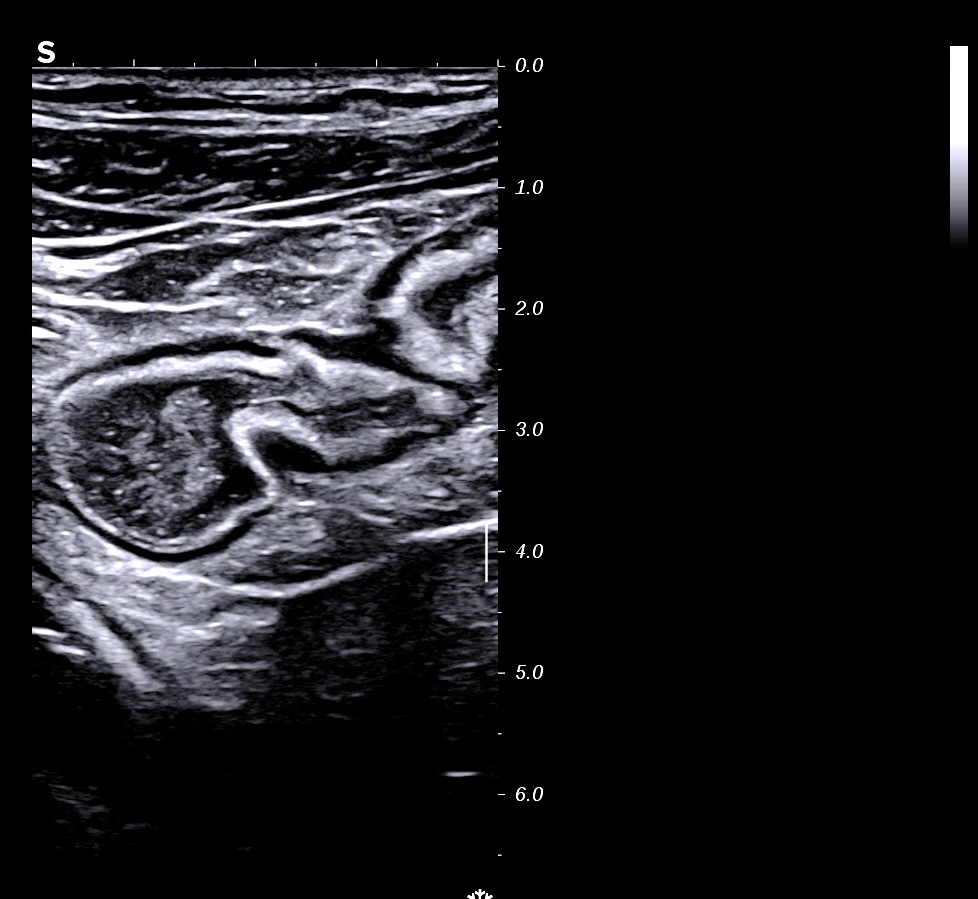

RCH classique, respect de la structure en couche,sous muqueuse très épaissie; musculeuse intacte

Classiquement dans la RCH, l'épaississement concerne les couches 2 et 3, c'est à dire muqueuse (hypoéchogène) et sous muqueuse (hyperéchogène) car il s'agit d'une maladie superficielle de la paroi, la musculeuse (4 ième couche hypoéchogène) est intacte et donc le bord externe est linéaire et régulier

L'épaississement prédomine à la 3 ième couche hyperéchogène (qui fait > 1/3 de la paroi)

Perte des haustrations (le bord externe du colon est rectiligne, lors de la cicatrisation on retrouve des haustrations)

La structure en couche est toujours conservée